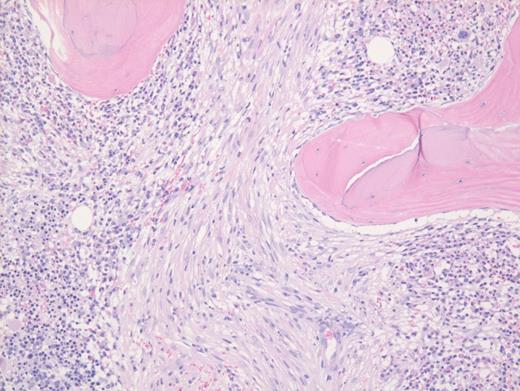

These results prompted a subsequent bone marrow biopsy. Peripheral blood smear showed rare abnormal circulating cells (Figure 1). Bone marrow core biopsy showed clusters of spindle cells adjacent to bony trabeculae (Figure 2) that were positive for CD117 (Figure 3). Scattered teardrop cells were also noted. Molecular testing by next-generation sequencing (NGS) detected diagnostic mutations.

Mast cell with metachromatic granules in circulation (Figure 1) with spindly clusters of compact mast cells in the biopsy (Figure 2) that are positive for CD117 (Figure 3) allows a diagnosis of systemic mastocytosis. These marrow spindly clusters of cells were also positive for mast cell tryptase and CD25. Mastocytosis is defined as multifocal infiltration by clonal proliferation of mast cells in one or more sites. They are broadly divided into cutaneous mastocytosis, systemic mastocytosis (SM), and mast cell sarcoma. The 2016 World Health Organization (WHO) classification of hematologic neoplasms separated them from myeloproliferative neoplasms. Cutaneous mastocytosis is restricted to the skin.

Neoplastic mast cells often assume a spindle shape on biopsy. All mast cells co-express CD117 and mast cell tryptase. However, when they express CD25, SM should be suspected. The mast cells in this case were positive for CD117, tryptase, and CD25 (not shown).